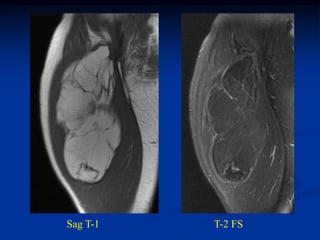

Case #1190.2 33 yearold female with painless lump at ankle for 1 year

Sag T-1 PD Gad